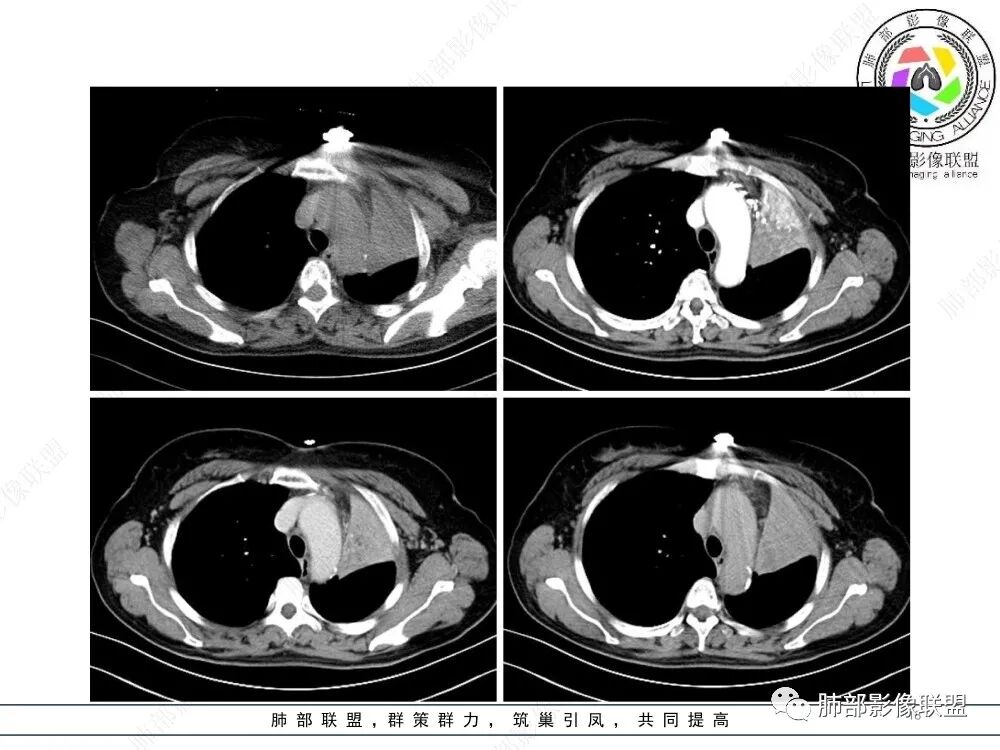

2、影像表现:正常肺背景,左肺上叶支气管腔内占位,上叶支气管截断,远端肺组织不张,强化差异衬托出肺门区结节影或块状影。增强扫描腔内占位轻中度不均匀强化,可见坏死,远端粘液栓,局部肺动脉受压、侵犯,纵膈淋巴结无明显肿大,无胸腔积液。

病灶腔内位主,局部膨隆凸向上叶支气管,两侧壁不清,病灶明显突出于壁外。

外形近端膨隆,远端收缩。

局部肺动脉受压明显,受压处似乎有点边界不清。

远端走形自然,提示远端不张,强化最明显处应该是单纯不张肺组织。

近端病灶内强化偏低,提示有侵犯。

综上,腔内占位明确,周围侵犯明确,支持支气管腔内恶性肿瘤,并阻塞性不张。